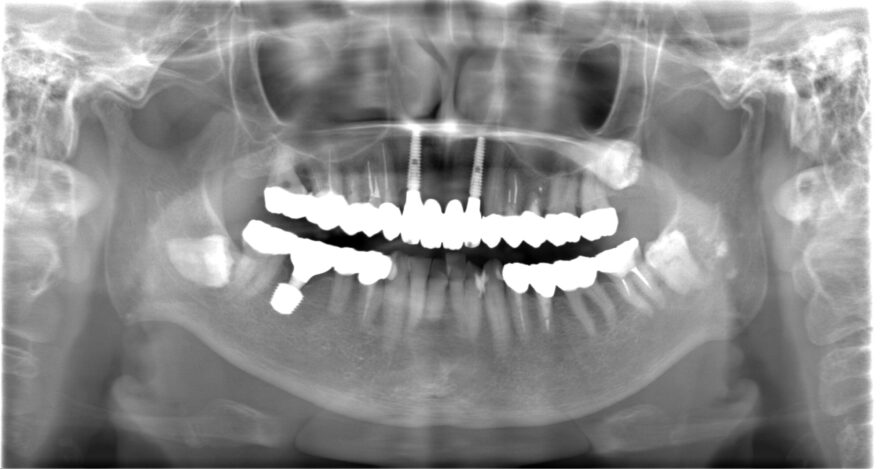

治療後のレントゲン写真

両サイドに2本のインプラントを埋め込み、4本の上部構造を支えるインプラントブリッジを患者様に提案しました。

埋め込むインプラントを4本ではなく2本にすることで、オペ後の腫れと痛みを少なく、治療費も少なくできます。